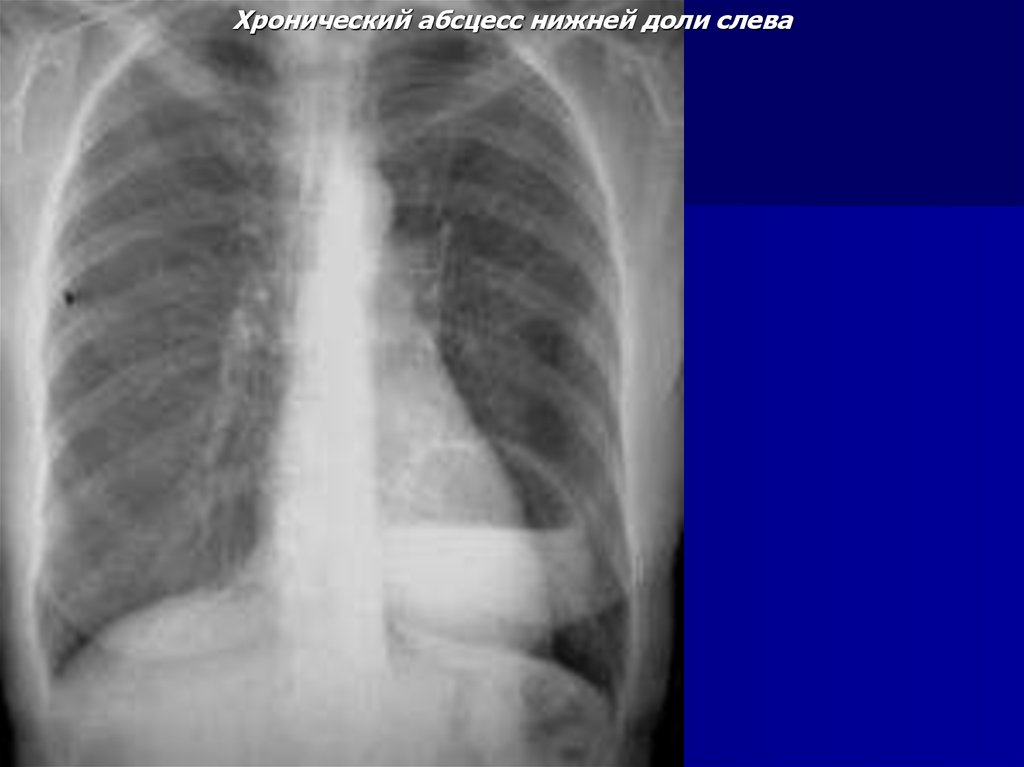

Хронический абсцесс нижней доли слева